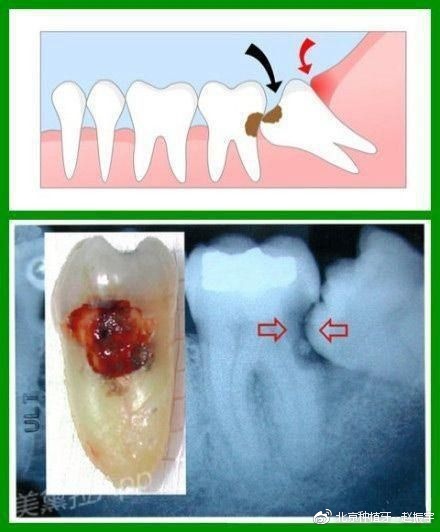

智齿到底是怎么回事?

智齿是哪个